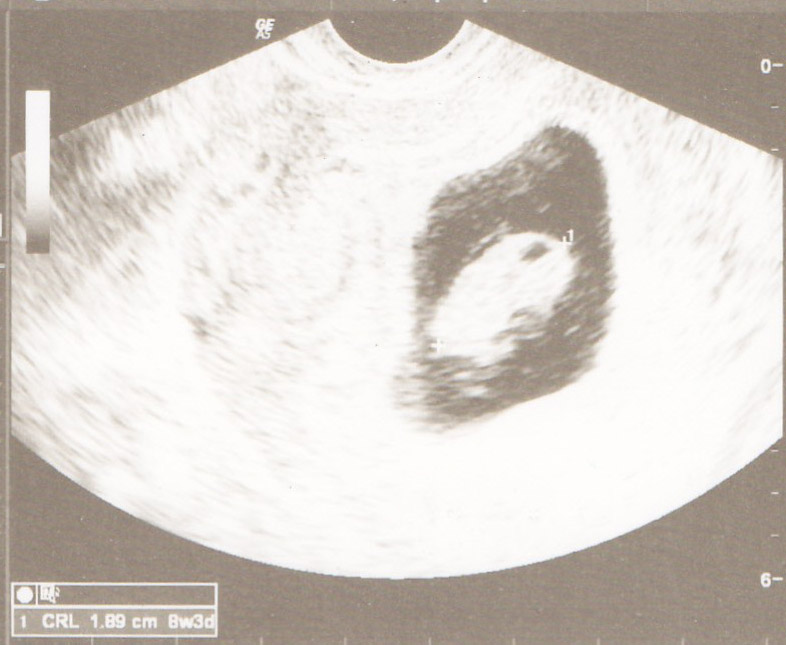

How far along are you?

8+4

Rants/Raves?

First appt and US yesterday! We got to see LO and the fluttering little heartbeat. <3 And s/he is right on track growth wise from my LMP so EDD remains the same (June 27). I thought it would make the pregnancy seem more real, but it's still incredibly surreal. I keep thinking we're going to be parents? Weird.... Also got the NIPT and next US scheduled so I feel better having that in place.